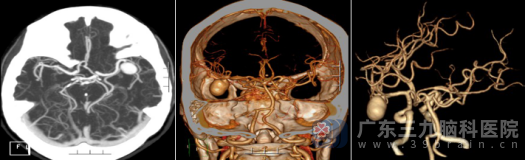

带着不安与疑惑,王女士来到广东三九脑科医院,找到了外十科欧阳辉教授。欧阳教授马上收她住院。进一步的CTA检查揭示了一个惊人的事实:她的左侧大脑中动脉M2段下干,竟然藏着一个大小约19.1×14.5毫米的大型动脉瘤!

经过近八小时的精雕细琢,外十科团队成功实施了“左侧大脑中动脉巨大动脉瘤夹闭术(孤立术)+动脉瘤切除术”。术后CTA显示:局部瘤体已完全消失,周围血管通畅,大脑血供良好。